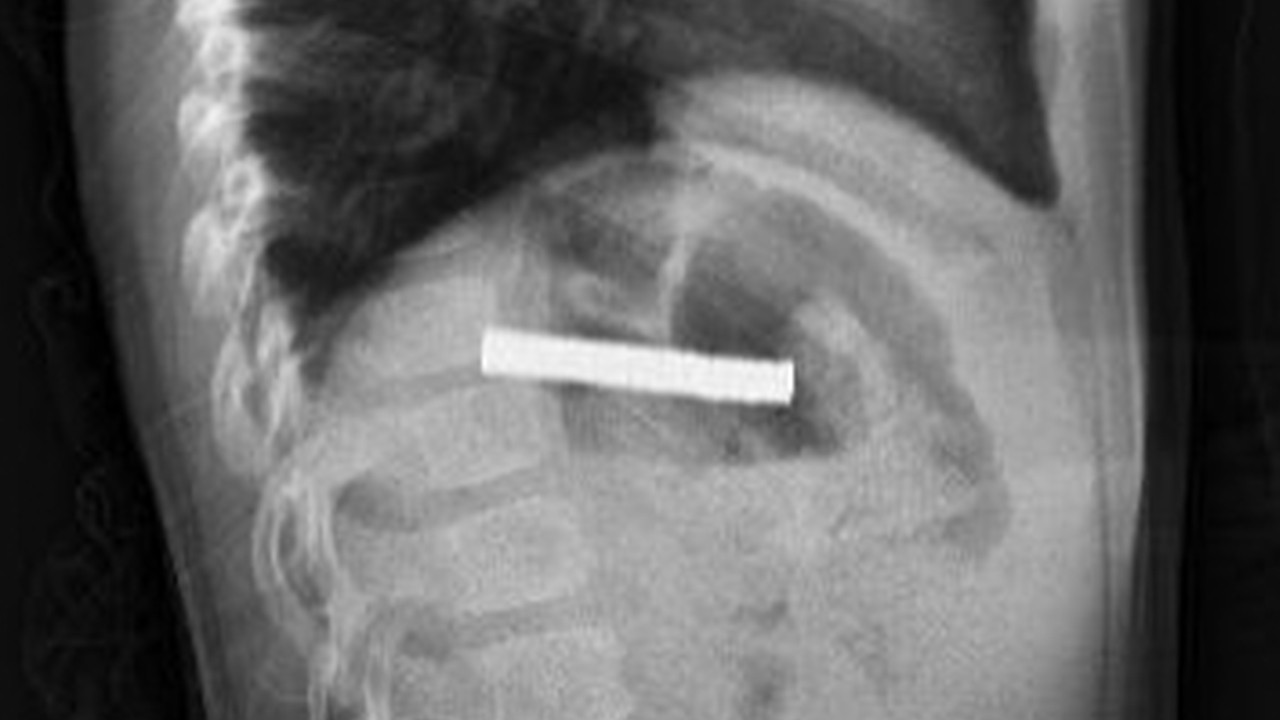

Erzurum’da 3 yaşındaki çocuk, evde oynadığı sırada 19 mıknatıs yuttu. Bir süre sonra rahatsızlanan çocuğun durumunu fark eden ailesi, hastaneye başvurdu. Yapılan ilk müdahalenin ardından çocuk, ileri tetkik ve tedavisi için Elazığ’daki Fırat Üniversitesi Hastanesi’ne sevk edildi. Fırat Üniversitesi Tıp Fakültesi Çocuk Gastroenteroloji, Hepatoloji ve Beslenme Bilim Dalı Başkanı Prof. Dr. Yaşar Doğan ve ekibi tarafından gerçekleştirilen operasyonla, çocuğun yemek borusuna yapışan 19 mıknatıs endoskopik yöntemle çıkarıldı. Mıknatısların, mide girişinde ve yemek borusunda zedelenmelere yol açtığı belirtildi. Çocuk tedavisinin ardından taburcu edildi.